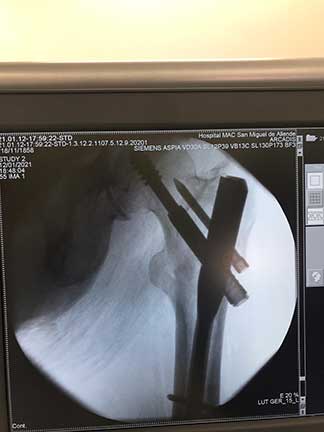

El tratamiento en pacientes adultos regularmente es quirúrgico, el cual se realiza con implantes de metal que recuperan la anatomía normal de la articulación similar a la previa fractura, los cuales pueden ser clavos, placas, tornillos o prótesis.

Cuidados después de la intervención

La intención de un tratamiento de fractura siempre es movilizar al paciente lo más pronto posible, los tiempos para movilizar al paciente puede ser desde el primer día del tratamiento hasta algunas semanas dependiendo del tipo de fractura, tipo de paciente y el implante utilizado.